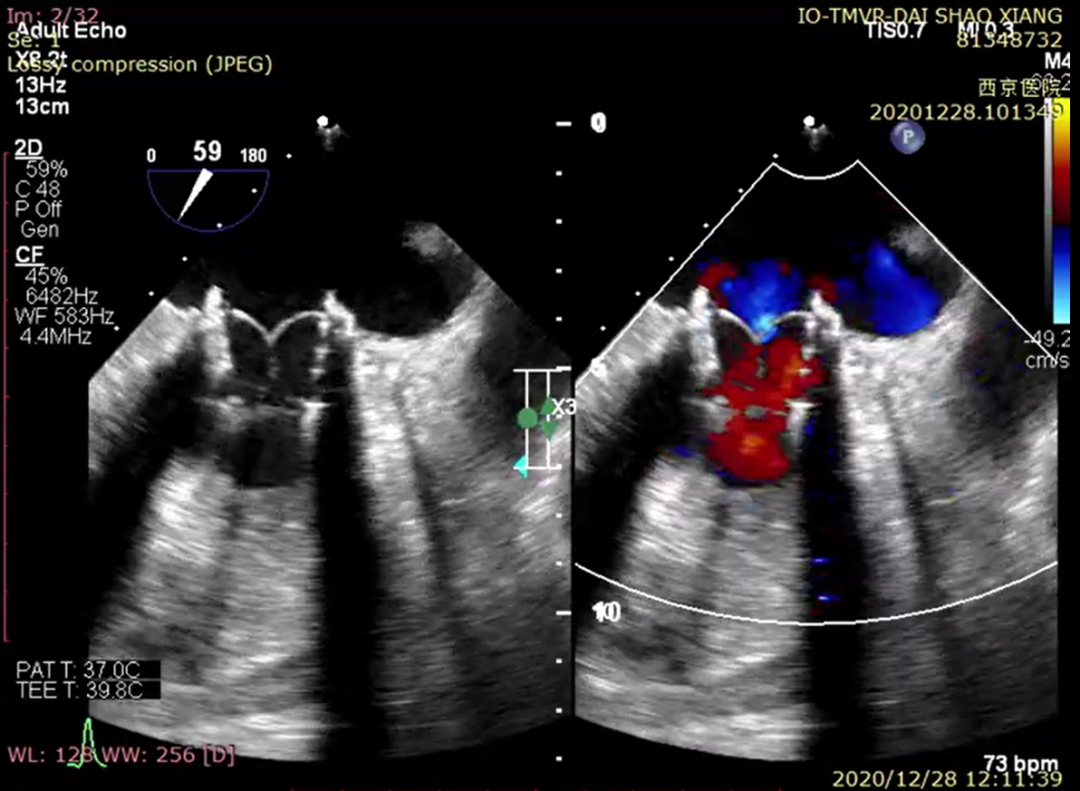

术后超声心动图

术后次日患者即下床正常活动,复查各项血液生化指标恢复良好,超声、CTA、3D打印等多模态影像评估结果显示二尖瓣“瓣中瓣”位置良好,二尖瓣血流速度无加速,未影响左心室流出道等重要解剖结构,顺利康复出院。